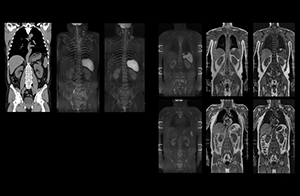

Recognizing the clinical utility of whole body MR imaging, radiologists at Kawasaki Saiwai Hospital (Kasawaki, Japan) began offering whole body diffusion weighted imaging (DWI) in 2009 for oncology patients. In 2012, the hospital installed a Philips scanner, the Ingenia 1.5T. The dStream digital architecture and highly linear gradients of Ingenia allowed them to switch to coronal – rather than axial – whole body DWI, and were key to developing a fast, high quality protocol that has led to increased referrals and decreased dependence on nuclear medicine imaging.

“When we limited the scan coverage to the area from neck to femur, we could fit more clinical information in approximately the same scan time. So, we added coronal mDIXON, sagittal T1-weighted, and sagittal STIR sequences to our examination, instead of performing only axial DWIBS and coronal single-shot TSE scans.” The single shot T2-weighted TSE images are used for morphology and compared to DWIBS images to identify T2 shine-through. Sagittal STIR images are used in patients with inflammation or bone metastasis.

“Switching to coronal DWIBS – rather than axial – further shortens scan time,” says Mr. Naka. “Important is that a dS SENSE factor of 5 shortens exam time while high image quality can be maintained, thanks to Ingenia’s dStream architecture.” He adds that the coronal orientation also avoids artifacts that are specific to combining axial images.

Kawasaki Sawai Hospital’s whole body protocol also includes an mDIXON FFE sequence. Because mDIXON provides images for four contrast types – water only, fat only, in-phase and out-of-phase – from a single acquisition, it is useful in many ways.